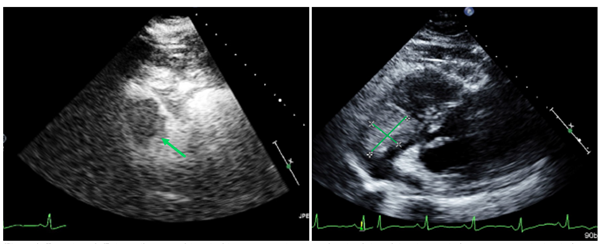

A 62-year-old Caucasian woman was admitted to the hospital with three months of worsened dyspneaon exertion, fatigue and unintentional weight loss of ten pounds. Labs showed iron deficiency anemia with hemoglobin down trended to 6.4g/dL and positive fecal occult blood test, normal CEA (1.5ng/mL) and CA 19-9 (7U/mL), with elevated LDH (541IU/L).CT scan of the chest, abdomen and pelvis revealed two non-obstructing small bowel masses(5.3cm jejunal mass and 12.3cm ileal mass), hypoattenuated right hepatic lesions, sub-centimeter right pulmonary nodules (up to 9mm), and a 3cm by 3cm by 4cm intracardiac mass at the tricuspid annulus(Figures 1A, 1C, 2A). MR of the liver revealed three right hepatic lobe lesions, measuring up to 1.3cm. Transthoracic echocardiogram confirmed the large mobile right atrial mass attaching below the anterior tricuspid valve leaflet and protruding into the right ventricle (Figure 3). Subsequent cardiac MRI characterized the right atrial mass as a mixture of tumor and thrombus. MRI brain revealed small subacute infarct in the left cerebellar hemisphere, but no intracranial metastasis.

Figure 3 Transthoracic echocardiogram with and without contrast demonstrates the right atrial melanoma lesion before treatment at the level of the tricuspid valve.

Dual checkpoint blockade with ipilimumab (3mg/kg) and nivolumab (1mg/kg) given intravenously was started on hospital day 18 with good tolerance. The patient was discharged after 40 days of hospitalization, with continued requirement for intermittent blood transfusions. Molecular testing was confirmed and expanded on via FoundationOne analysis of the original tissue biopsy, revealing tumor mutational burden of 14 mutations/Mb, homozygous loss of CDKN2A and CDKN2B, and TP53 1245S in addition to NRAS Q61R and MSI stable status. She proceeded to complete four cycles of ipilimumab/nivolumab dosed every three weeks, followed by maintenance PD-1 inhibitor, and improved clinically with less frequent blood transfusion requirement. At six months since diagnosis, updated scans and echocardiogram continued to show treatment response with stable to reduced sizes of the cardiac and mesenteric masses (Figure 1B, 1D, 2B).